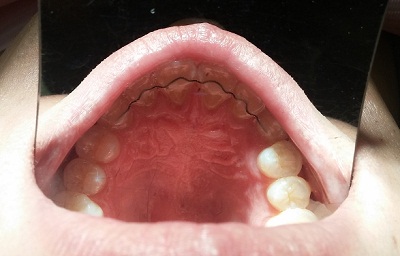

(25화 3월 중순 촬영 아래에서 위로 찍은 사진)